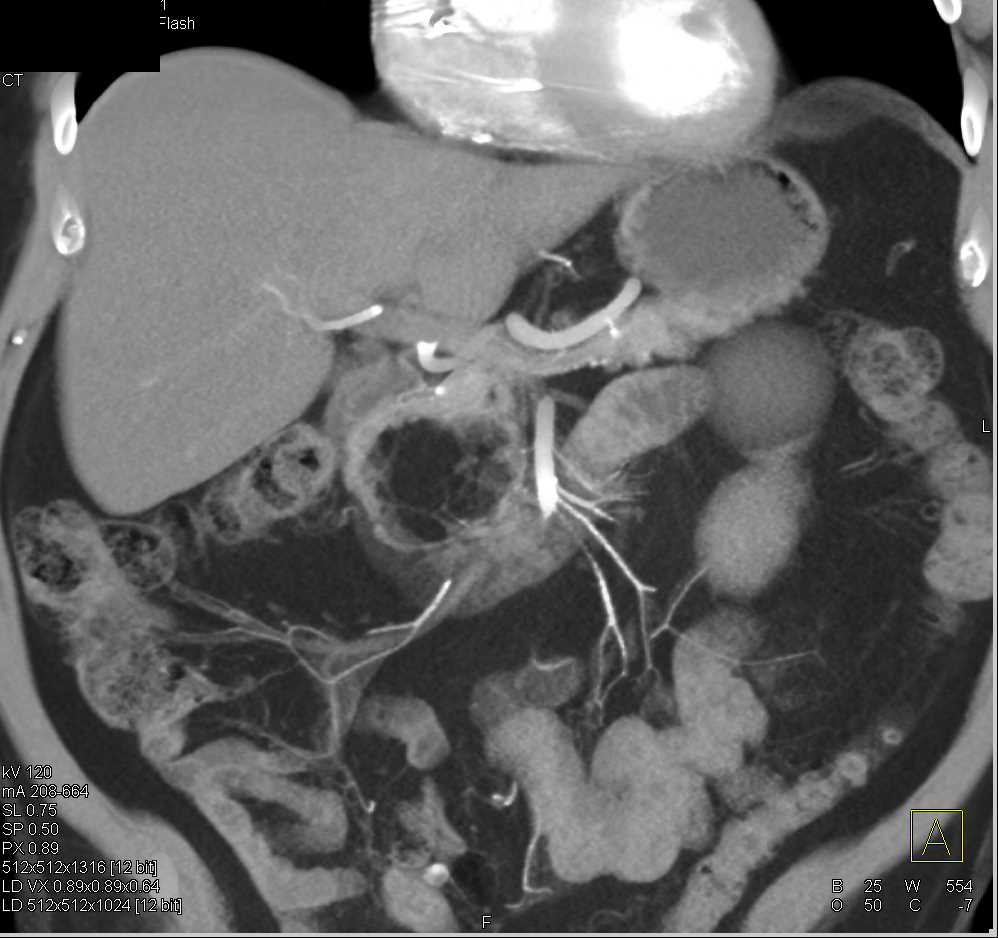

Hemoperitoneum S/P Whipple Procedure